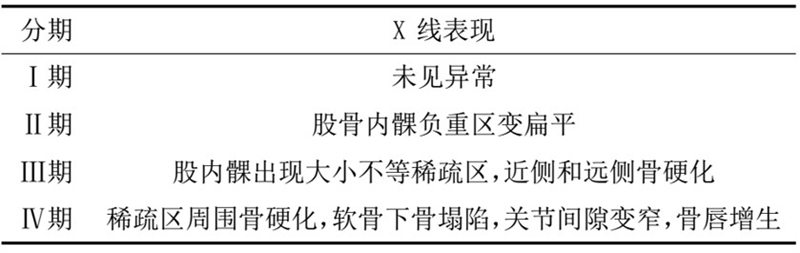

目前SONK诊断最常用的分期方法是1979年Koshino提出的分期法。Koshino分期基于临床和影像学的结果,将SONK分为四个阶段:

Ⅰ期:患者有膝关节症状,但影像学正常;

Ⅱ期:X线显示负重区变平,软骨下信号升高,周围有骨硬化;

Ⅲ期:受影响区域扩大和软骨下塌陷;

Ⅳ期:病变周围骨硬化和髁突周围骨赘形成的退行性阶段。

1979年Koshino分期